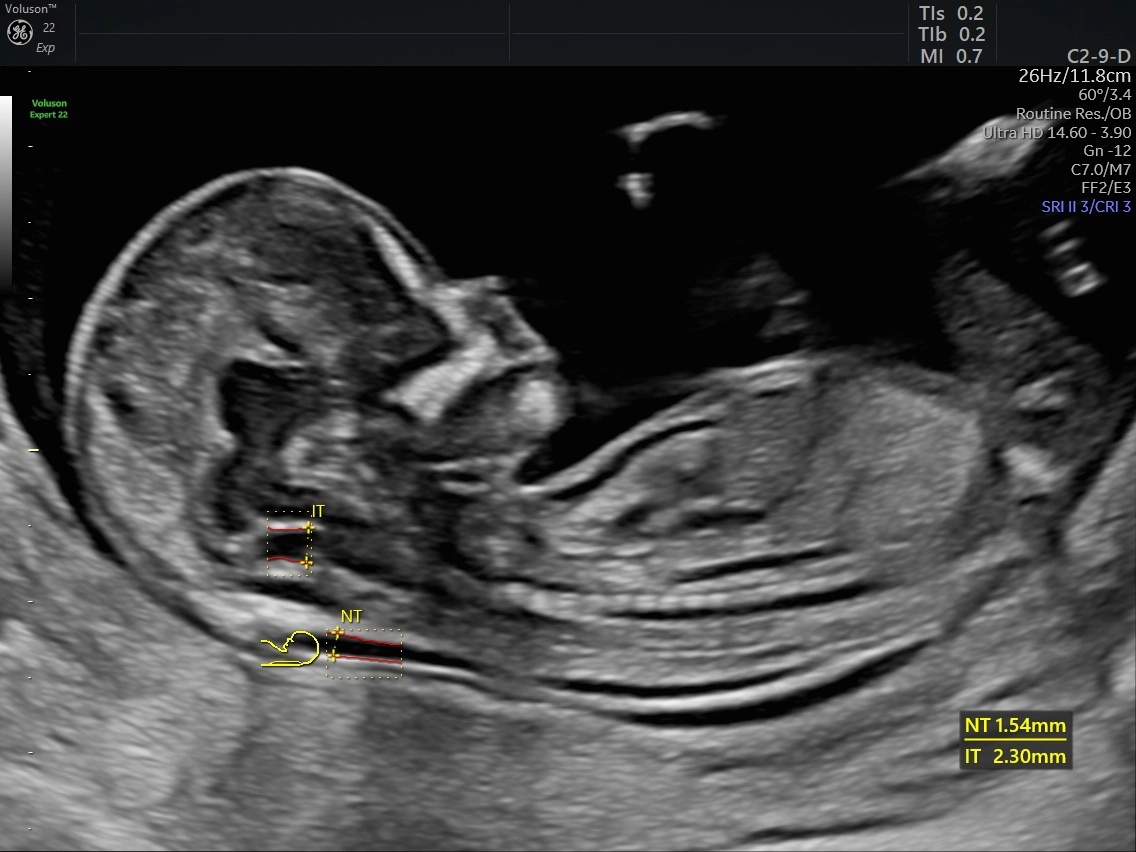

Đo độ mờ da gáy (Nuchal translucency)

16/03/2026